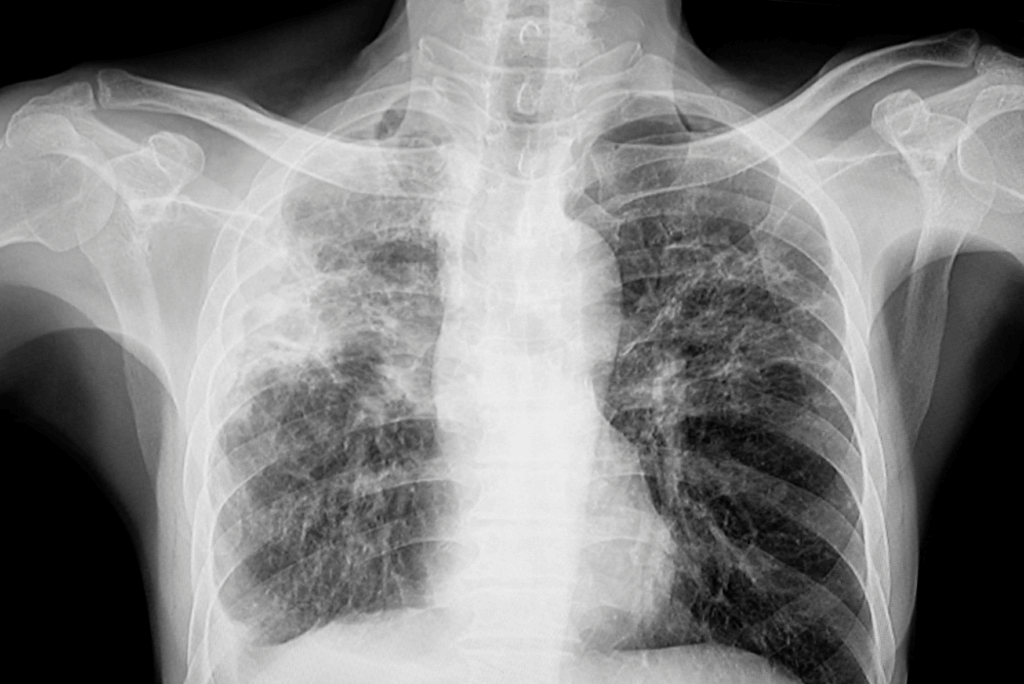

Chest X-ray showing pulmonary tuberculosis (TB) with predominant involvement of the upper lobes, which may affect the left, right, or both lungs.